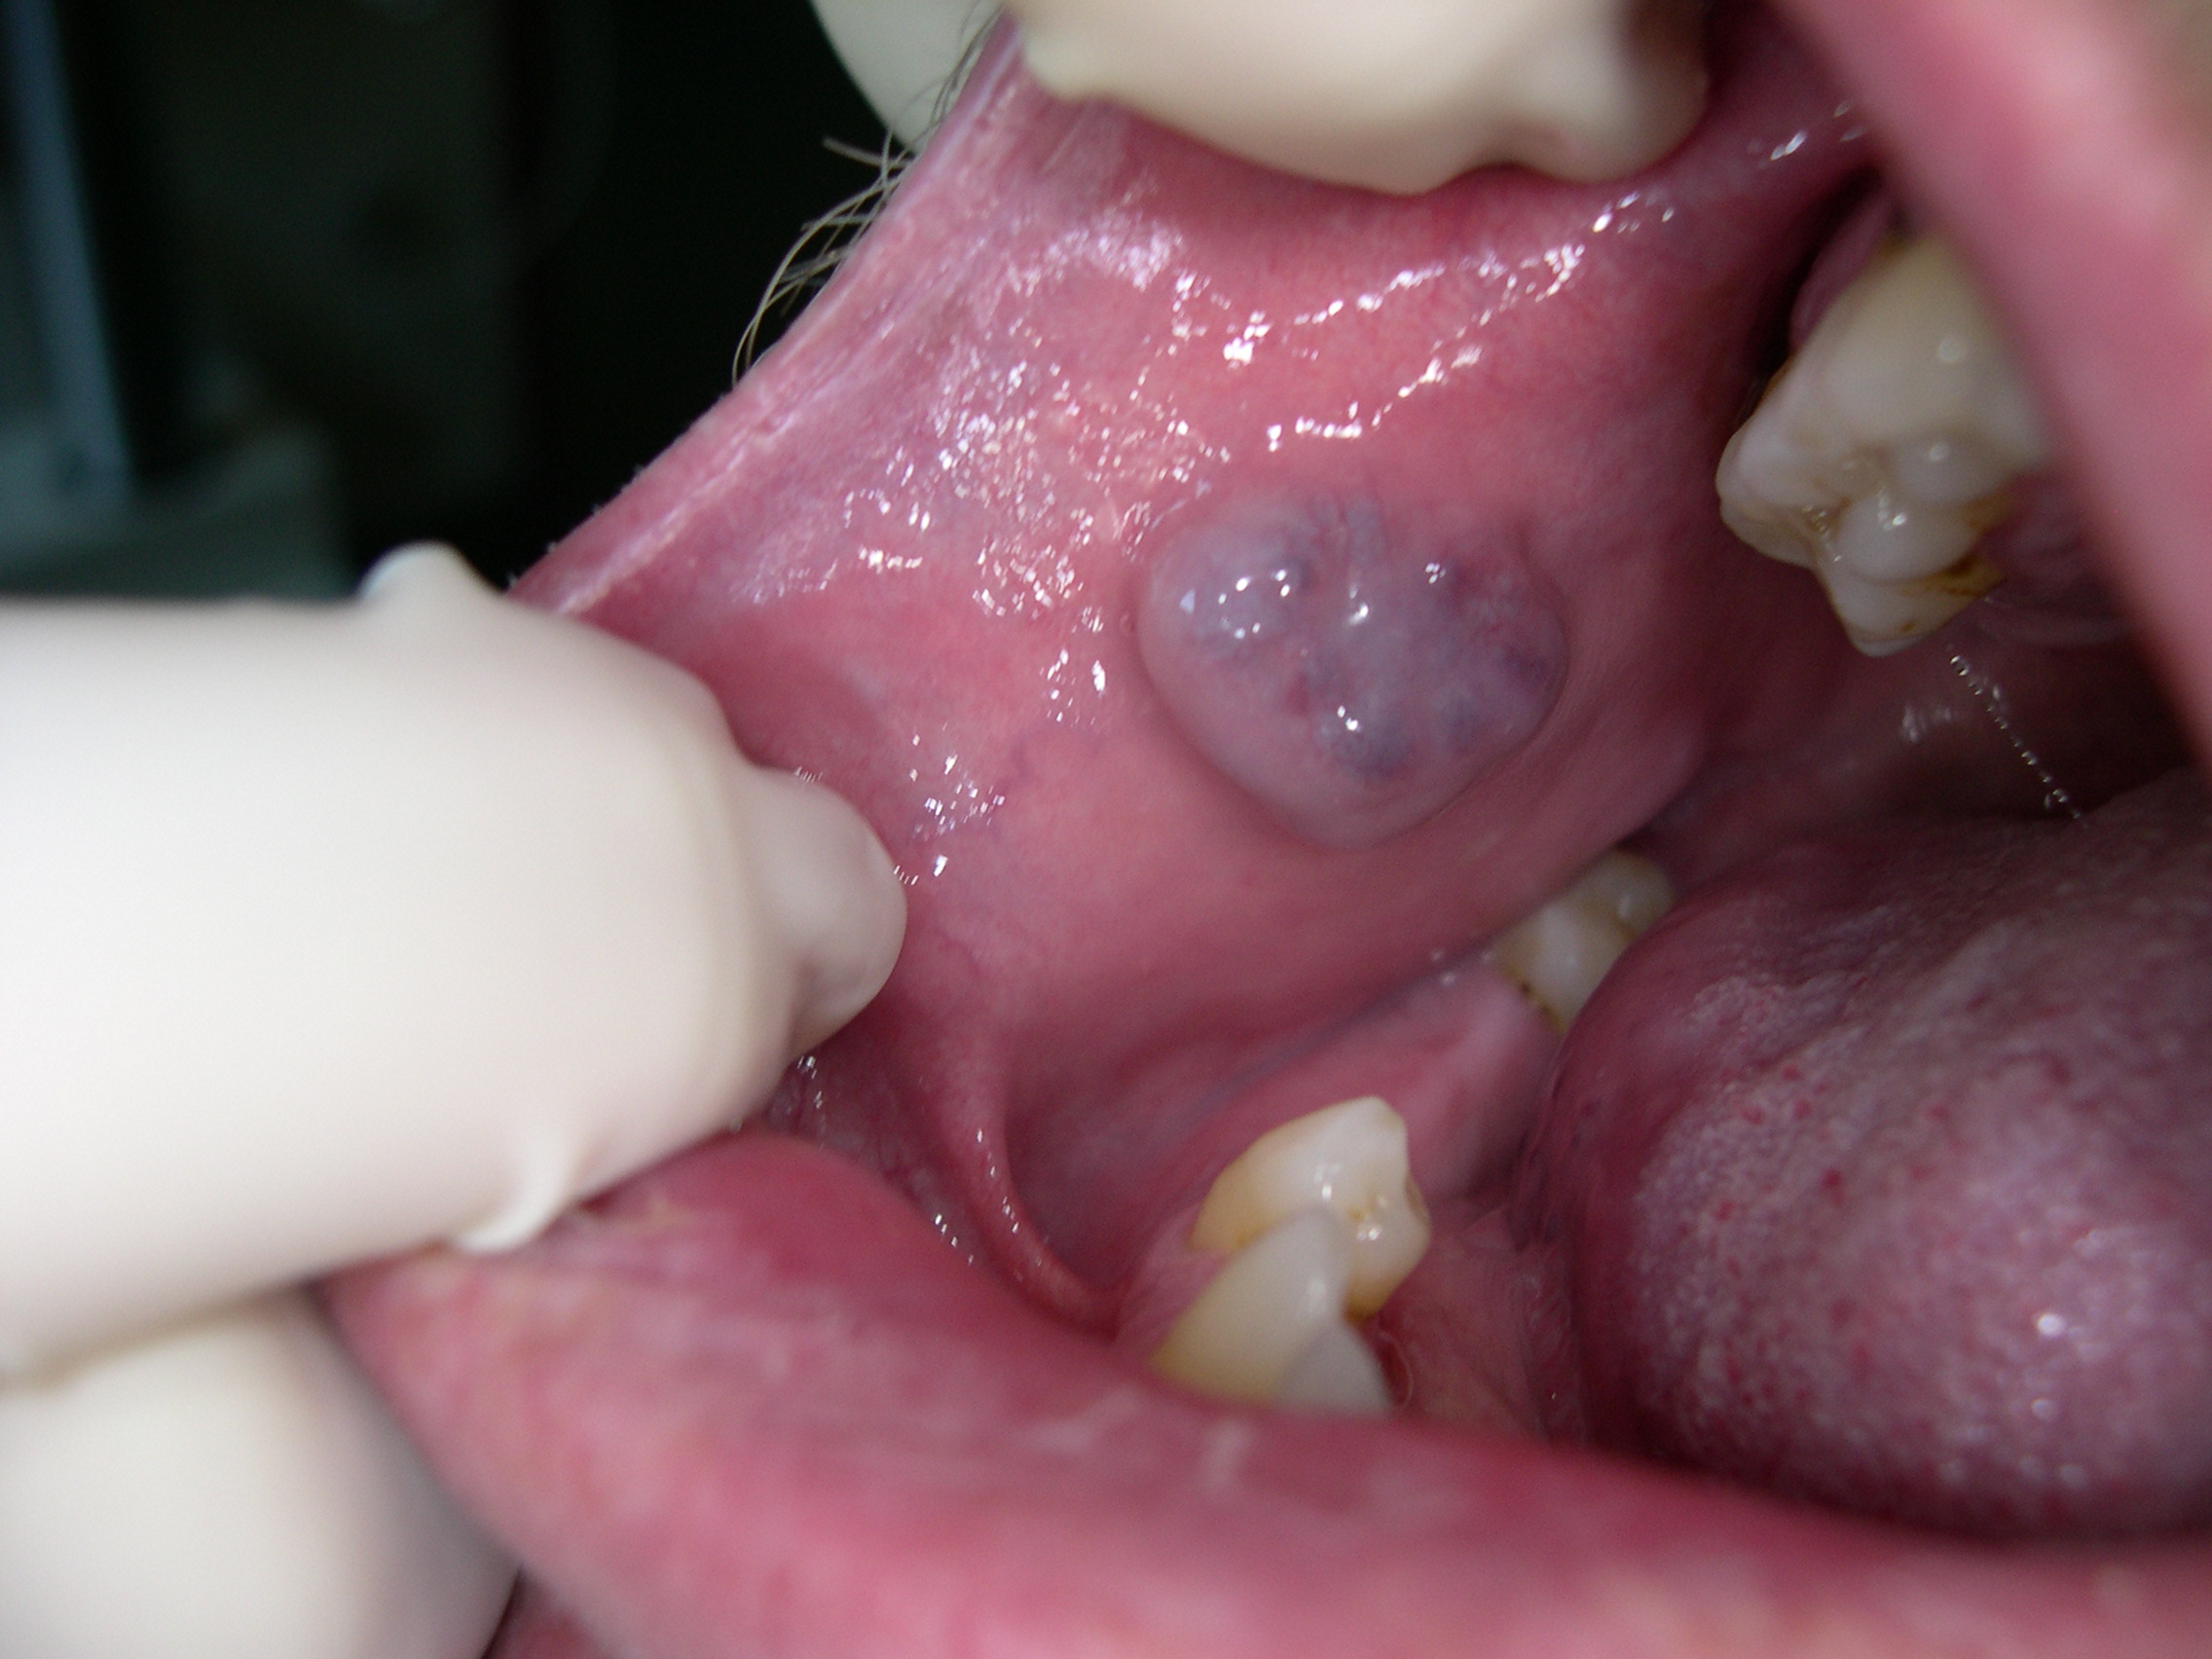

Ugotovili smo, da imate žilno malformacijo, v žargonu največkrat imenovano hemangiom. To je benigna žilna tvorba, se pravi, da ni rakasta, lahko pa povzroča kar nekaj nevšečnosti. Včasih je moteč občutek v ustih, včasih pacienta moti izgled, hemangiom lahko moti nošnjo proteze, lahko večkrat nadležno zakrvavi, nekatere neprijetno boli... Le redkokdaj so hemangiomi lahko nevarni, predvsem tisti večji, ki jih napaja večja arterija in lahko smrtno nevarno zakrvavijo. Vendar so ti le izjemno redki in se jih lotevamo drugače.

Opravimo jo z Nd:YAG laserjem. Kratica laserja pomeni itrij:aluminijev kristal, v katerem so ioni neodimija. V tem kristalu nastaja visokoenergetska laserska svetloba, ki nato potuje po optičnem vlaknu do posebnega ročnika, s katerim optično vlakno in s tem laserski žarek usmerjamo v poljubno smer. Nd:YAG laser ima to lastnost, da potuje dokaj globoko v tkivo, do 7 mm pod površino. Na svoji poti skozi tkivo oddaja laserski žarek energijo v obliki toplote, s tem dvigne temperaturo tkiva in ga skoagulira oz. zakrkne, zato se proces imenuje laserska fotokoagulacija. Pravzaprav se podobno zgodi jajčnemu beljaku, ki v ponvi zakrkne.

Z optičnim vlaknom, iz katerega izstopa laserski žarek, počasi potujemo tik nad hemangiomom, ki ob tem pobledi in se skrči. Poseg navadno traja le eno do dve minuti. Običajno ni niti minimalne krvavitve.